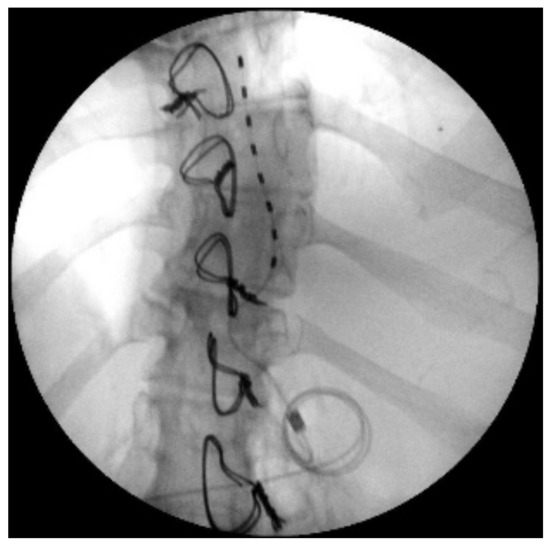

- -